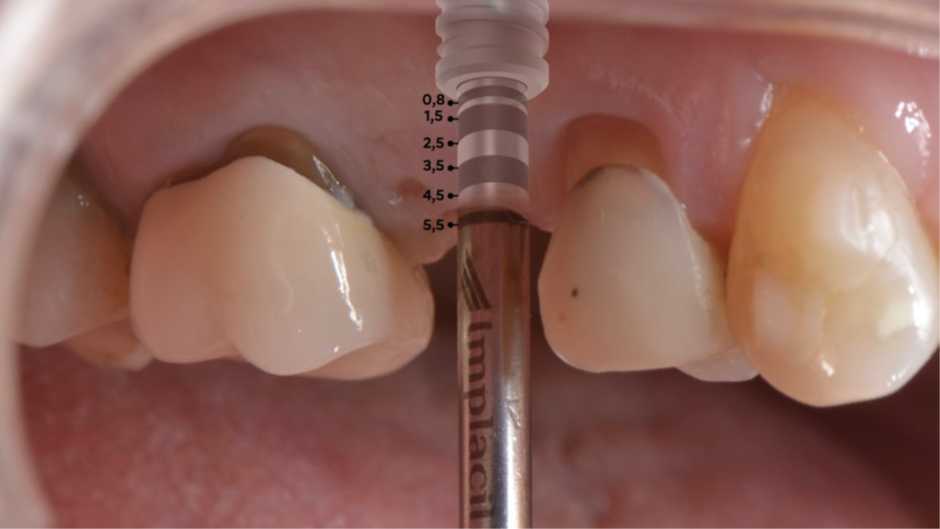

Para fazermos a coroa definitiva, precisamos posicionar a margem gengival semelhante aos dentes adjacentes. Nesse caso, usamos o túnel check de prótese CM para escolha da cinta do pilar (Figura 7). Temos que tomar muito cuidado em saber onde posicionar a margem gengival vestibular da coroa sobre implante, pois quando temos muita espessura de mucosa, a marcação do túnel check pode “confundir” no momento da seleção da cinta do pilar (Figura 8). O pilar de escolha para esse caso foi o Ideale 3.3×4 e foi planejado para ser instalado como uma cinta de 2,5mm, a fim de que a margem da coroa sobre implante fique semelhante à margem dos dentes adjacentes. Então, o pilar Ideale reto 3.3×4 com a cinta de 2,5mm foi instalado (Figura 9) para ser usado como pilar definitivo e fazer uma coroa provisória sobre o implante. A diferença de tamanho entre o diâmetro cervical do dente natural e o encaixe do implante pode resultar em um perfil inadequado da coroa. Se o perfil for subcontornado, não haverá pressão contralateral ou suporte para a mucosa, e as partículas de alimentos podem ficar retidas.

Figura 7 – Túnel check de prótese CM para escolha da cinta do pilar com muita espessura da mucosa.

Figura 8 – Túnel check de prótese CM com as marcações.